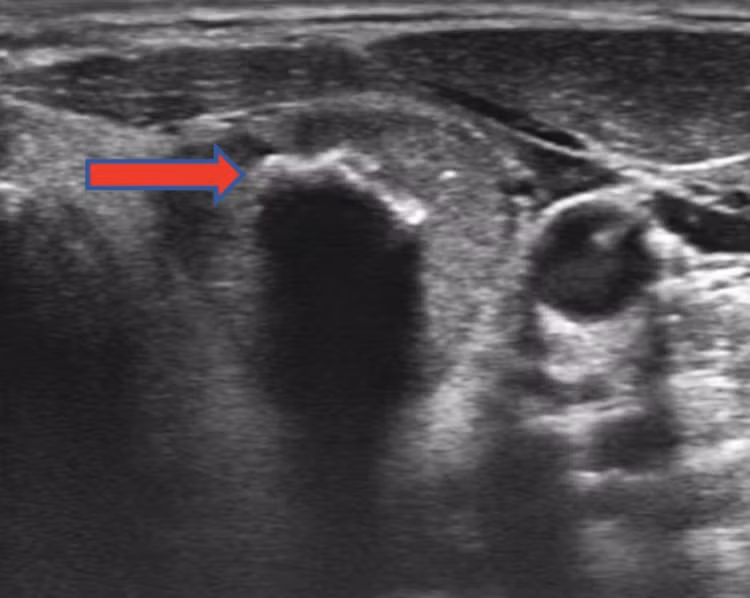

Cần phân biệt kết quả siêu âm phát hiện các vi vôi hóa hay là vôi hóa lớn? Một trong những đặc điểm siêu âm quan trọng nhất gợi ý ung thư là sự hiện diện của các vi vôi hóa, được nhìn thấy dưới dạng các điểm sáng nhỏ có kích thước ≤ 1 mm, xuất hiện trên ảnh siêu âm tuyến giáp.

Do đó, khi có mặt trên siêu âm, vi vôi hóa đại diện cho vùng ung thư tuyến giáp thể nhú. Ngược lại, vôi hóa lớn là những mảng canxi lớn, với kích thước > 1 mm (có thể đến 5-10 mm) có thể xuất hiện bên trong nhân giáp hoặc ở ngoại vi của nhân (gọi là vôi hóa dạng vỏ trứng/ vành), thường được nhìn thấy dưới dạng các điểm sáng lớn trên siêu âm.